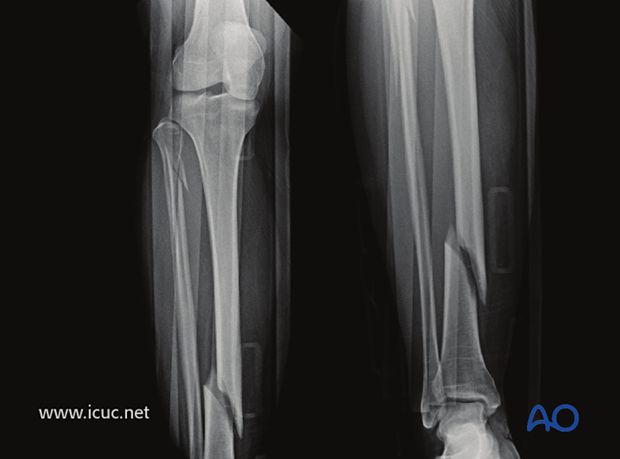

What type of fracture is this?

Spiral

Due to rotation causing fracture